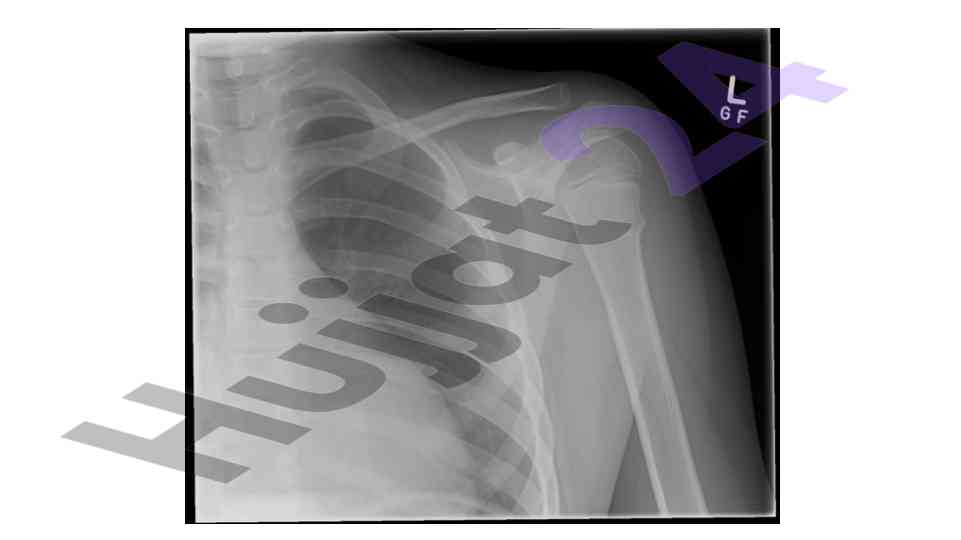

Muskuloskeletal system in pediatrics

An overview of the muskuloskeletal system with a focus on pediatric applications and implications for treatment.